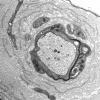

PERIPHERAL NEUROPATHY

18 HEREDITARY DISORDERS

Charcot-Marie-Tooth 3 (CMT-3) (2)